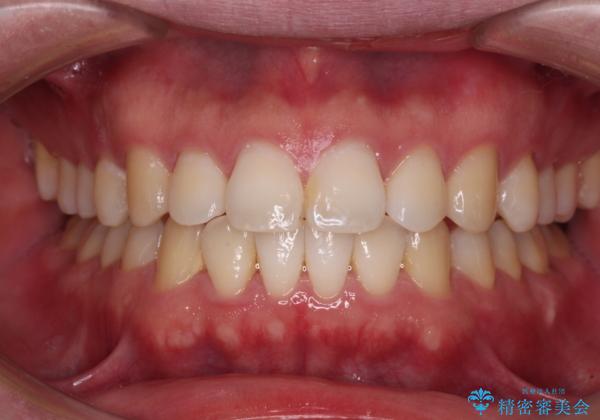

インビザラインで奥歯の咬み合わせと前歯のデコボコを改善

- 前歯のデコボコと奥歯の咬み合わせを気にして来院された患者様です。

前歯のデコボコはインビザラインで十分に対応可能と判断できましたが、咬合力が強いため、臼歯(特に右側)の交叉咬合はインビザライン単体では困難と思われました。

まずはインビザライン単体で矯正治療を開始し、交叉咬合が改善されない場合にはアンカースクリューなどの使用を検討することとしました。

インビザライン単体では右側の交叉咬合を解消することができなかったため、アンカースクリューを併用して咬合を改善させました。